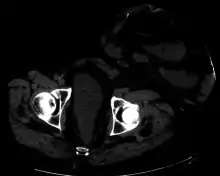

A colostomy is an opening (stoma) in the large intestine (colon), or the surgical procedure that creates one. The opening is formed by drawing the healthy end of the colon through an incision in the anterior abdominal wall and suturing it into place. This opening, often in conjunction with an attached ostomy system, provides an alternative channel for feces to leave the body. Thus if the natural anus is unavailable for that function (for example, in cases where it has been removed in the fight against colorectal cancer or ulcerative colitis), an artificial anus takes over. It may be reversible or irreversible, depending on the circumstances.

Placement of the stoma on the abdomen can occur at any location along the colon, but the most common placement is on the lower left side near the sigmoid where a majority of colon cancers occur. Other locations include the ascending, transverse, and descending sections of the colon.[4]